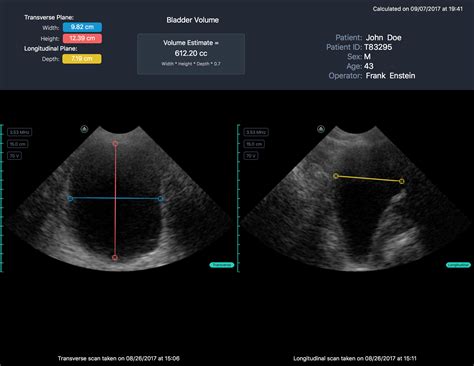

Ultrasound imaging is one of the most commonly used methods to calculate bladder volume. This non-invasive technique uses sound waves to create images of the bladder, allowing healthcare providers to measure its dimensions accurately. The formula commonly used to estimate bladder volume from ultrasound measurements is:

Volume = (Length × Width × Height) × 0.52

Here’s a step-by-step guide to using ultrasound imaging to calculate bladder volume:

• Position the patient in a supine or semi-recumbent position.

• Apply ultrasound gel to the lower abdomen.

• Use a transabdominal ultrasound probe to visualize the bladder.

• Measure the length, width, and height of the bladder in centimeters.

• Apply the formula to calculate the bladder volume.